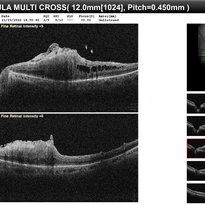

• Epiretinal Membrane causing Macular Pucker.

Dec 11 2022 by Anjana Mirajkar, MS Ophthalmology

OCT of LE in a 65 year old male case of Epiretinal Membrane causing Macular Pucker.

Photographer: Dr. Anjana Mirajkar -Retina Foundation, Ahmedabad.

Condition/keywords: epiretinal membrane (ERM), macular pucker